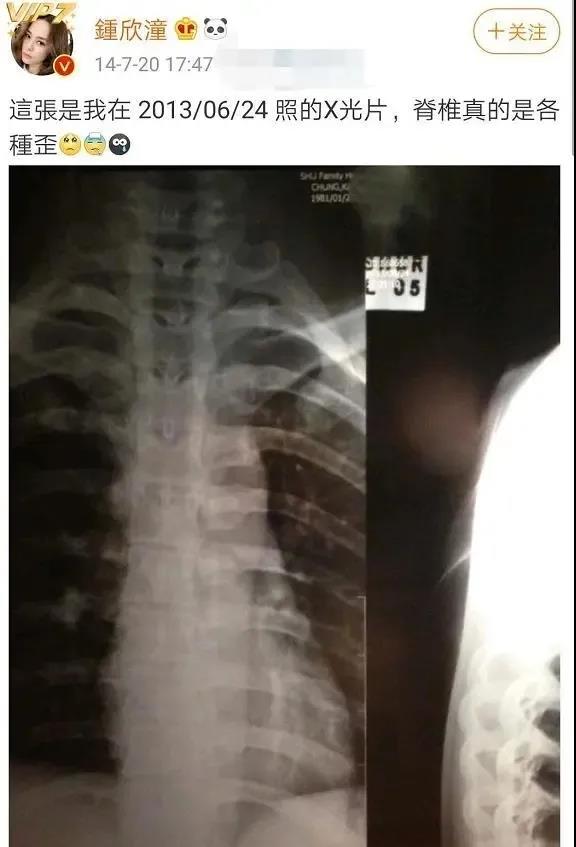

其实阿娇一直以来都是十分敬业的人,而因为工作太拼命,她也常常将自己弄得浑身是伤。在此前接受采访时阿娇就曾表示过:“之前脊柱歪了,很痛,痛了十个月,拍完剧要找医生把骨头拍正,之后又跌伤了尾骨,坐和站都很痛,要学空中瑜伽。”受到网友的质疑后还曾晒出过自己的X光片。